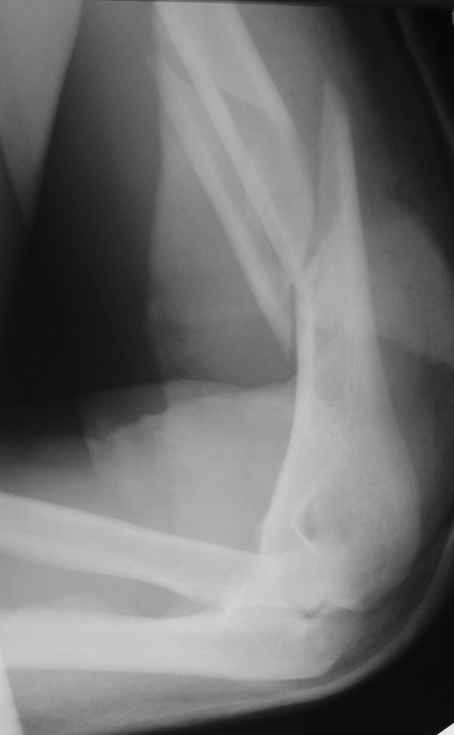

Огромное спасибо всем принимающим участие в дискуссии. Вначале отвечу на поступавшие персональные вопросы: 1. обстоятельства травмы - соревнования по армрестлингу (от себя замечу, что у военных нередкая травма в последнее время! На мой взгляд это связано с вовлечением в это дело неподготовленных людей - командирам нравится, т.к. в плане реквизита намного легче организовать чем традиционное перетягивание каната...). 2. в отношении провокационной составляющей - она присутствует, но лишь в той степени в какой любое инициирование дискуссии несет в себе элемент провокации... 3. про актуальность консервативного лечения - мне кажется это актуально всегда и при любой локализации если врач владеет методом, например, часто наблюдал великолепные функциональные результаты консервативного лечения переломо-вывихов голеностопных суставов... Тут только надо помнить, что "консервативное" это тоже лечение (контроль, тяги, перекладывание повязок), а не просто накладываем гипс и через энное время говорим, что не получилось и берем на операцию.

Теперь непосредственно по больному. Лечим функциональной повязкой, добились вот чего (приложение). Будем признательны за дальнейший комментарий - мое мнение, что можно продолжить без операции.